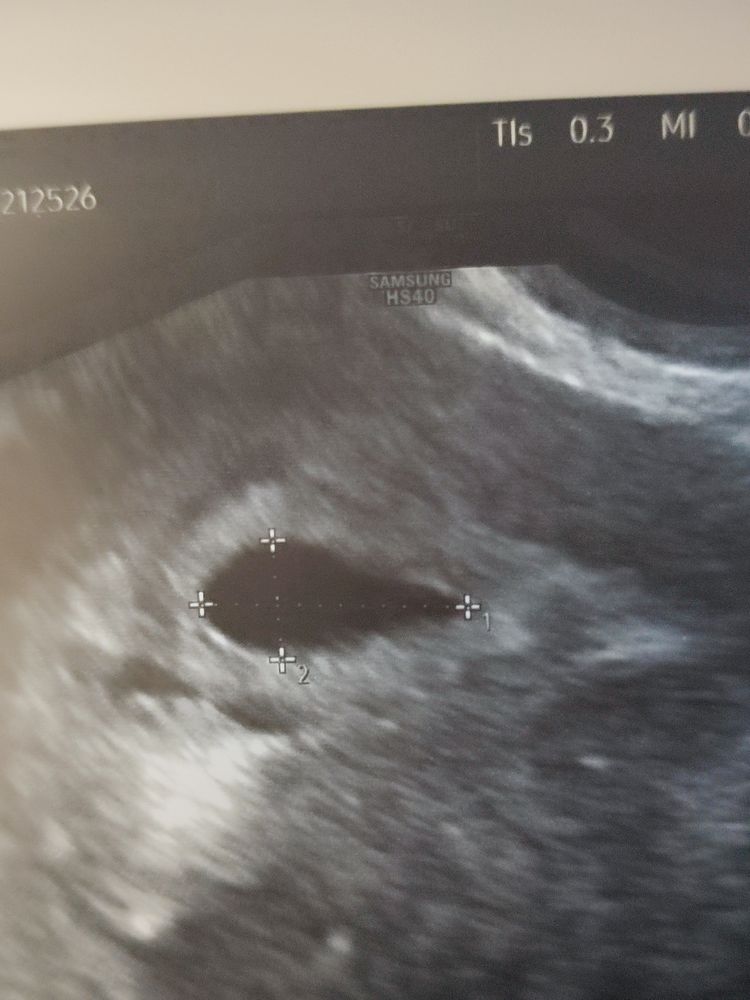

Виктория , вот тут кажись получше видно. Вчера в принципе сказали, что лялечка уже начала появляться, но пока сложно дифференцируема. Жду воскресенья с трепетом 🫣 Изображение